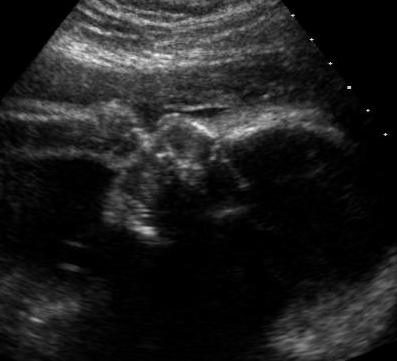

Get in touch with your local colleges and find out if their sonography/ultrasound technician programs need volunteers! I got in touch with mine and went yesterday and I spent TWO HOURS just watching my baby

it was amazing! She was sucking her fingers and toes, blinking and she even yawned when they were hovering over her face at one point! Talk about goosebumps!! They sent me home with a CD full of pictures (46 to be exact) and even scheduled me to come back later for a different class to practice on me.

You have to have some patience because it's students doing the scans so they aren't trained professionals yet but they did really well for me and took all the pictures I wanted. The instructor came around at the end of the class and took some really great pictures for us. The class was practicing OB measurements so they only needed pregnant women from 24-30 weeks but they have other classes where they find organs later on and things like that.